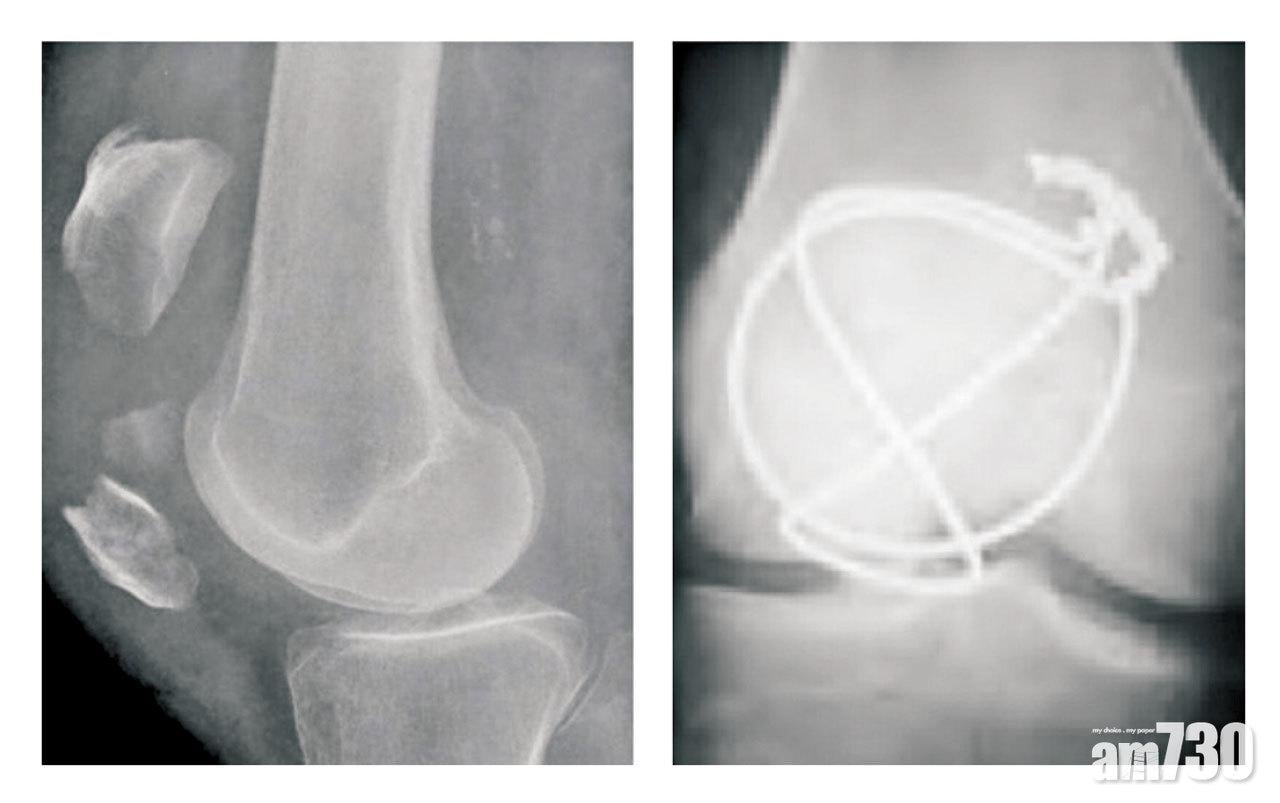

透過X光,可評估骨折的形態。如果骨折屬穩定且無移位,便只需要打石膏或佩戴支架來保持膝部伸直,以防股四頭肌將骨折拉開,讓髕骨可在4至6星期內自然愈合。但拆石膏後,膝關節會變得僵硬,股四頭肌亦有所萎縮,須接受物理治療來達至康復。倘若骨折屬橫斷或粉碎性,並且明顯移位,甚至膝部喪失伸展機制,便須做開放性復位及內固定術。手術通常會用鋼線,以環紮以及張力帶方式固定骨折,有需要時更輔以鋼針或螺絲。術後膝關節一般可自由活動,至於鋼線則建議在一年左右移除,否則會出現金屬疲勞而斷裂。

這種以鋼線紮成的張力帶,在力學上能夠把骨折分離的張力,轉化為互相壓迫的力量,從而促進骨折愈合。情況恍似孫悟空頭上,那個逼使他跪低屈服的「金剛圈」:你愈想擺脫掙開,便會愈牢牢緊箍。